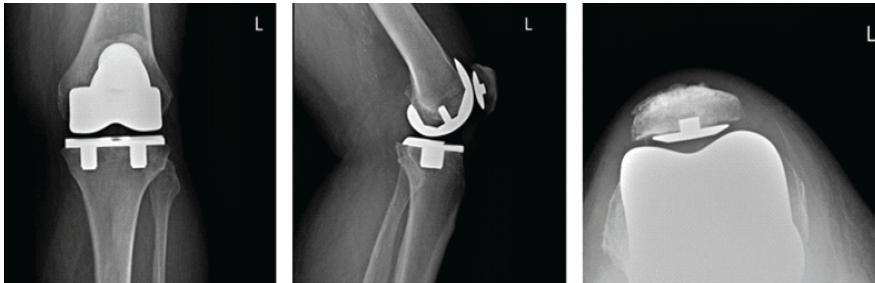

Figure 2: First post-operative X-rays. Three radiographic views of the left knee are visualized on the patient’s post-operative visit, including anteroposterior, lateral, and patellofemoral views, respectively. These radiographs demonstrate a press-fit total knee arthroplasty in place, well fixed, and well aligned, without periprosthetic fracture.

A post-operative X-ray showed the knee to be in appropriate alignment without evidence of complication (Fig. 2). The patient was transferred to the post-anesthesia care unit (PACU) in good condition, having tolerated the procedure well. Due to the patient’s high quality bone and relatively young age, a press-fit implant was chosen over the more traditional cemented implant, including: A standard width, size 8, Zimmer Persona CR Press-Fit Femoral Component, a size F, 2 peg, Press-Fit, Zimmer Persona tibial baseplate, a size 10 Zimmer Persona Medial Congruent Polyethylene Insert, and a size 38 Zimmer NexGen Press-Fit Patella. The patient continued to present for routine follow-up without evidence of complication for nearly 2 years until he returned to the clinic, stating that he had never been pleased with the operation. He complained of pain while standing, and at times, a sensation of “catching” and “giving out”. The patient underwent a normal physical exam. Three radiographic views of the left knee were examined for potential abnormalities. AP, lateral, and patellofemoral views of the left knee at this time demonstrated a failed patellar component with a shear fracture of the single peg prosthesis (Fig. 3). These findings were shared and discussed with the patient, who agreed to proceed with revision of the patellar component.